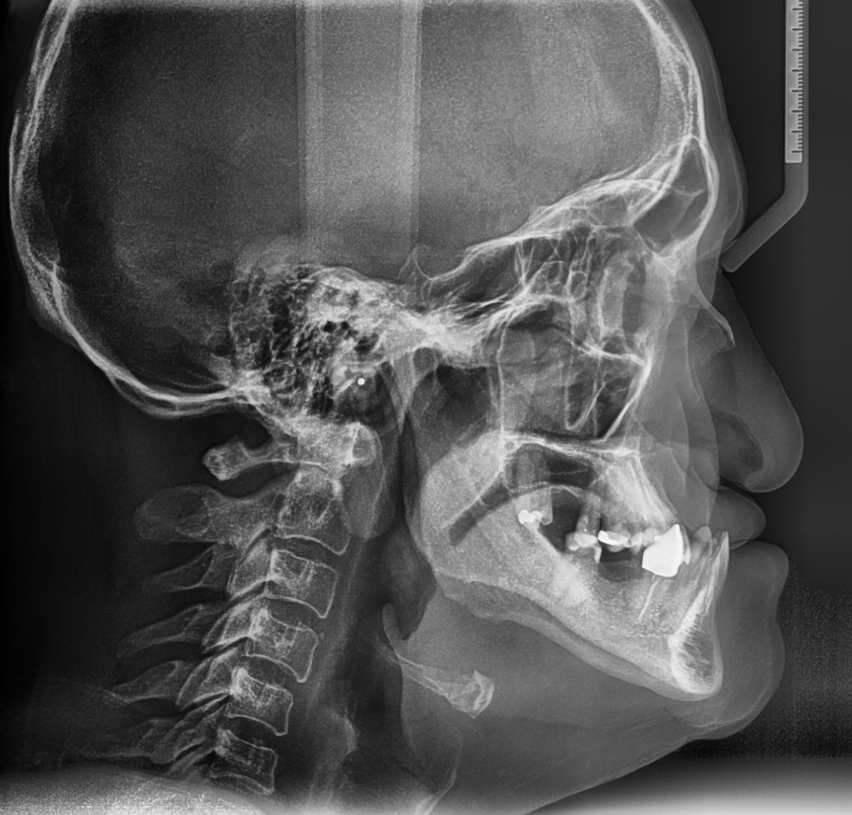

X-ray of a human skull showing a fracture in the jaw and dental issues.

Ortodoncia quirúrgica ortognática

La ortodoncia quirúrgica ortognática combina brackets con cirugía de mandíbula para corregir desequilibrios significativos de mordida, mandíbula o faciales que no pueden tratarse solo con ortodoncia. Este enfoque coordinado mejora tanto la función como la estética facial. Trabajando en estrecha colaboración con un equipo quirúrgico, la ortodoncista garantiza una planificación precisa para lograr resultados estables y duraderos.